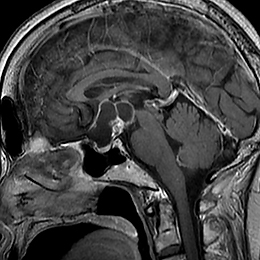

良性腫瘍の手術前

手術後